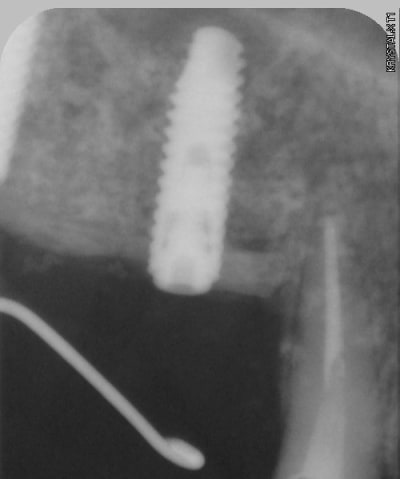

curetage (deux bonnes heures) dépose des deux vis d'ostéo et de l'implant en 16, nettoyage implant en 14/15 (axe un peu limite pour cause structure osseuse) et 17.

photos montrant le hiatus greffe/os et pose avec vitalos à la fin